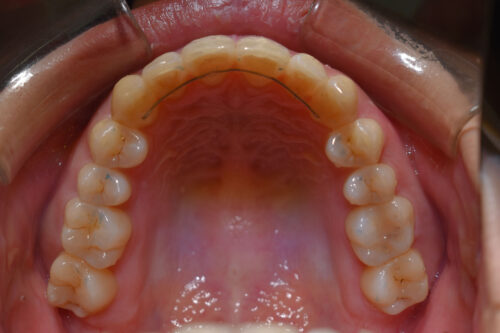

本症例も

矯正治療の精密検査後

非抜歯矯正治療計画を立案しました。

ワイヤー矯正治療11か月後です。

全額矯正治療 88万円、3~4週に一回来院

歯科矯正用アンカースクリュー(デュアル・トップオートスクリュー)上顎左右2本(25000円x1本分 提携医院にて)

ワイヤー期間 11か月, 17回来院

マウスピース型カスタムメイド矯正歯科治療を用いた矯正歯科治療装置を利用した矯正治療 5か月間 33000円、

本症例のように

屋根のように 上下の歯が 唇側に傾斜しており

口元が出っ歯に見えるのを気になさる患者様も多くいらっしゃいます。

昔は 第一小臼歯を4本抜歯して 矯正治療をしましたが、

今は 歯科矯正用アンカースクリュー(デュアル・トップオートスクリュー)を利用する

ことで

歯を抜かなくても 歯列全体を後方へ移動することができるようになりました。